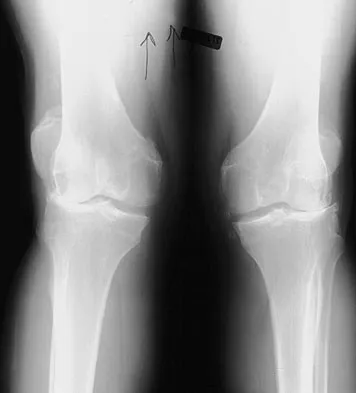

AAOS Sports Medicine Board Review (Set 2): Knee, Shoulder & Ankle Injuries

Master the AAOS & ABOS boards with high-yield practice MCQs for Set 4. This set covers advanced topics in hip…

Master the AAOS & ABOS boards with practice MCQs for Set 3, covering hip and knee arthroplasty, joint reconst…